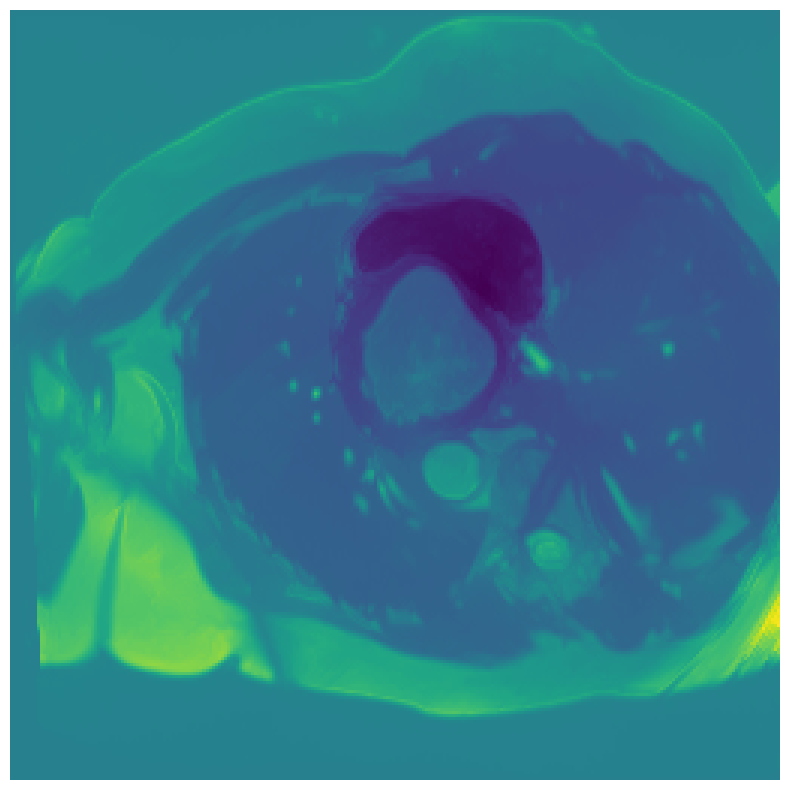

We normalize the volumes and resize the slices to pixels. As the official dataset comes with full annotations, we create a synthetic point ground truth. This is done by first randomly choosing the centers of the point annotations within the class masks, followed by filling an ellipse with axes lengths of and (in pixels) around each center. The intersections of these elliptic discs with the underlying full annotations are then used as our point ground truth. See Figure 2 for an example of the created weak annotation mask. The point annotations are created for every slice, one for each foreground object present in the slice.

5.1 Segmentation of cardiac structures

The average 3D Dice scores and HD95 values on the ACDC test set are given in Table 2, and boxplots in figures 4 and 5 show the distributions. We see that, in terms of DSC, the proposed strategy of using intensity-aware distances withing boundary loss performs better than simply using the Euclidean distance, with the best results achieved by using the strictly intensity based MBD. The HD95 however favors the original version of , which may be do to its smoother predictions and less fragmentation and oversegmentation. The CRF-loss results are significantly worse in both metrics.

In Figure 3 we show the 3D DSC validation curve evolution for a single run. The CRF-loss seems to have converged to a low DSC value, while all settings combining CE and boundary loss reach values close to the full supervision in the beginning of the training and then slowly collapse towards to the point annotations. The MBD version stands out, degrading slower, thus providing a wider range of potentially good models for evaluation.

Qualitative comparison

In Figure 6 we provide qualitative results on a number of randomly chosen test set slices. Upon visual inspection, we can observe that training with the intensity-aware distances (particularly with and ) follows the image gradients better and is better at recovering the underlying shape than the Euclidean version. The CRF-loss seems to recover the shape of the myocardium and left ventricle to some extent, but fails entirely on the right ventricle.